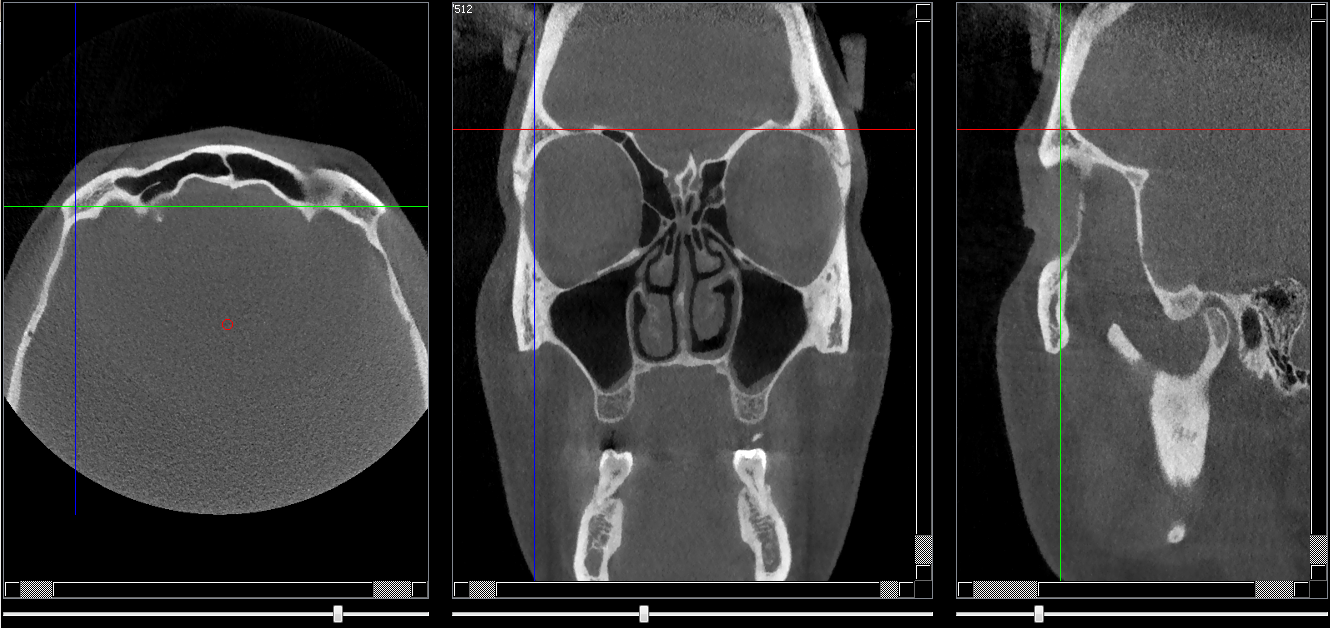

Structures osseuses

Os frontal

Repères anatomiques

- Coupe transversale

- Début : Os pariétal

- Fin : Processus zygomatique

- Coupe frontale

- Début : La lame criblée de l'éthmoide

- Fin : Os nasale

- Coupe saggitale

- Début : Processus zygomatique

- Fin : Suture fronto-éthmoidale

Infos sur l'image

- Auteur : Pr Bourzgui

- Co-auteur : Dr Makoure

- Affiliation : Orthopédie dento-faciale

- Date production : 2019